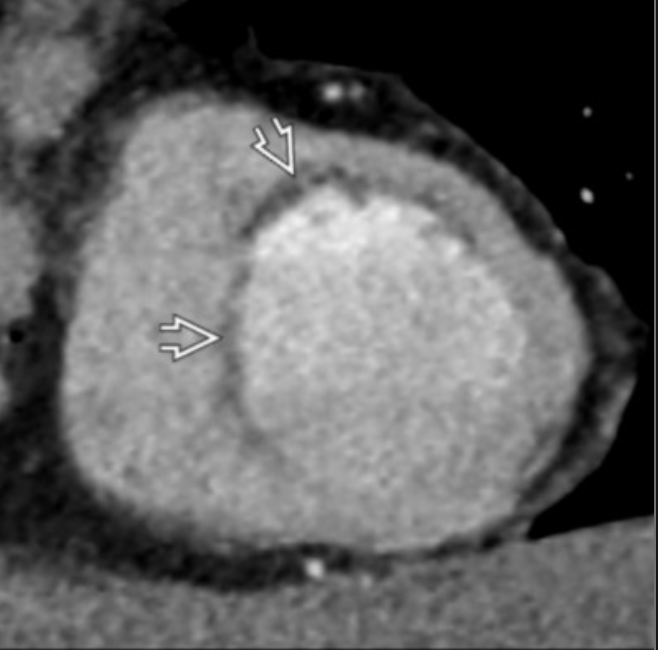

PT with exertional CP

Short axis images

show subendocardial fatty metaplasia, almost dx of prior MI , here in LAD distribution